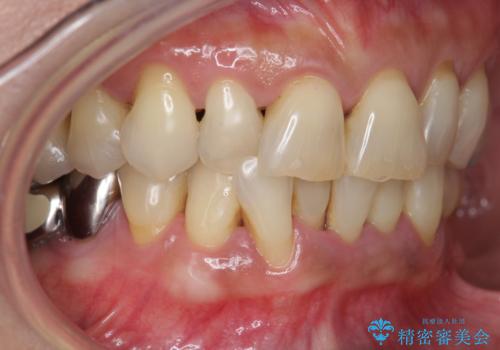

前歯のすれ違いによる歯周病を矯正治療で改善

- 下顎前歯のグラつきがどんどん悪くなり、痛くて噛めなくなってきたことの改善を希望され来院されました。

下顎前歯の1本は前歯よりも前に出てしまい後ろからの力を受けることで、周囲の骨も吸収しグラつきも大きくみられます。